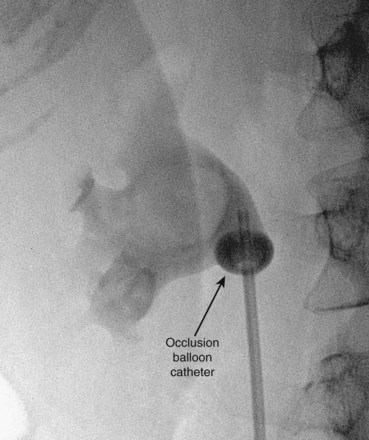

), and a guidewire can be passed from below and grasped by the nephroscope to establish through-and-through access from the external urethral meatus to the percutaneous entry site. A dual-lumen catheter can be placed as well. The small caliber of either catheter, however, does not provide much outflow from the kidney and may not prevent stone or tumor fragments from passing into the ureter along the catheter. A ureteral occlusion balloon catheter, which incorporates an approximately 15-Fr spherical balloon on the distal tip, more consistently prevents material from migrating down the ureter. The balloon should be carefully inflated in the renal pelvis, making sure the balloon is not in the ureter—which could lead to ureteral rupture—and then gently pull down to occlude the ureteropelvic junction (Fig. 47–12). Another alternative is to place a ureteral access sheath (usually 11 to 15 Fr) over a retrograde-inserted guidewire (Landman et al, 2003). The large outer diameter of the sheath effectively prevents particles from passing around the sheath into the ureter, and the large inner diameter affords excellent outflow of small stone particles. The disadvantages of employing a ureteral access sheath include the potential ureteral trauma from passing such a large device into the ureter and clogging of the catheter lumen by oversized stone fragments.

Figure 47–12 Occlusion balloon inflated and snugged down at ureteropelvic junction of contrast-filled upper tract collecting system.